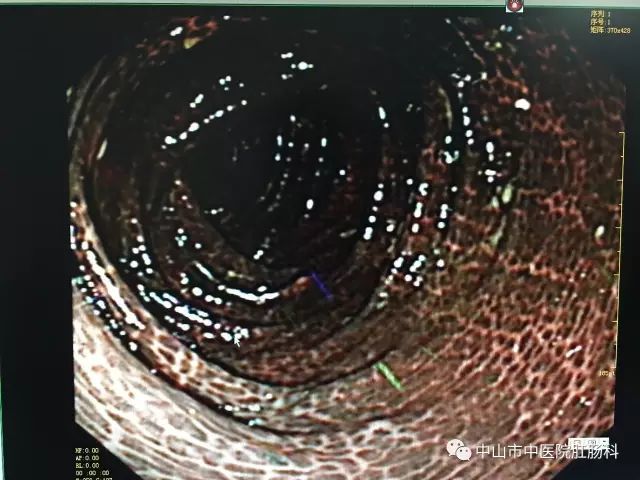

医生说,这样的肠粘膜改变,称之为“大肠黑变病”,在日常检查过程中检出率不低,但是像这位患者这样黑的,实属罕见。而正常的肠子,是粉红粉红、血管纹理分明的,如下图:

镜下表现为结肠黏膜光滑、完整,可见浅棕色、棕褐色或黑色的色素沉着,呈条纹状、斑片状、虎皮状改变,可网络状间断或连续分布,肠腔明显变暗。